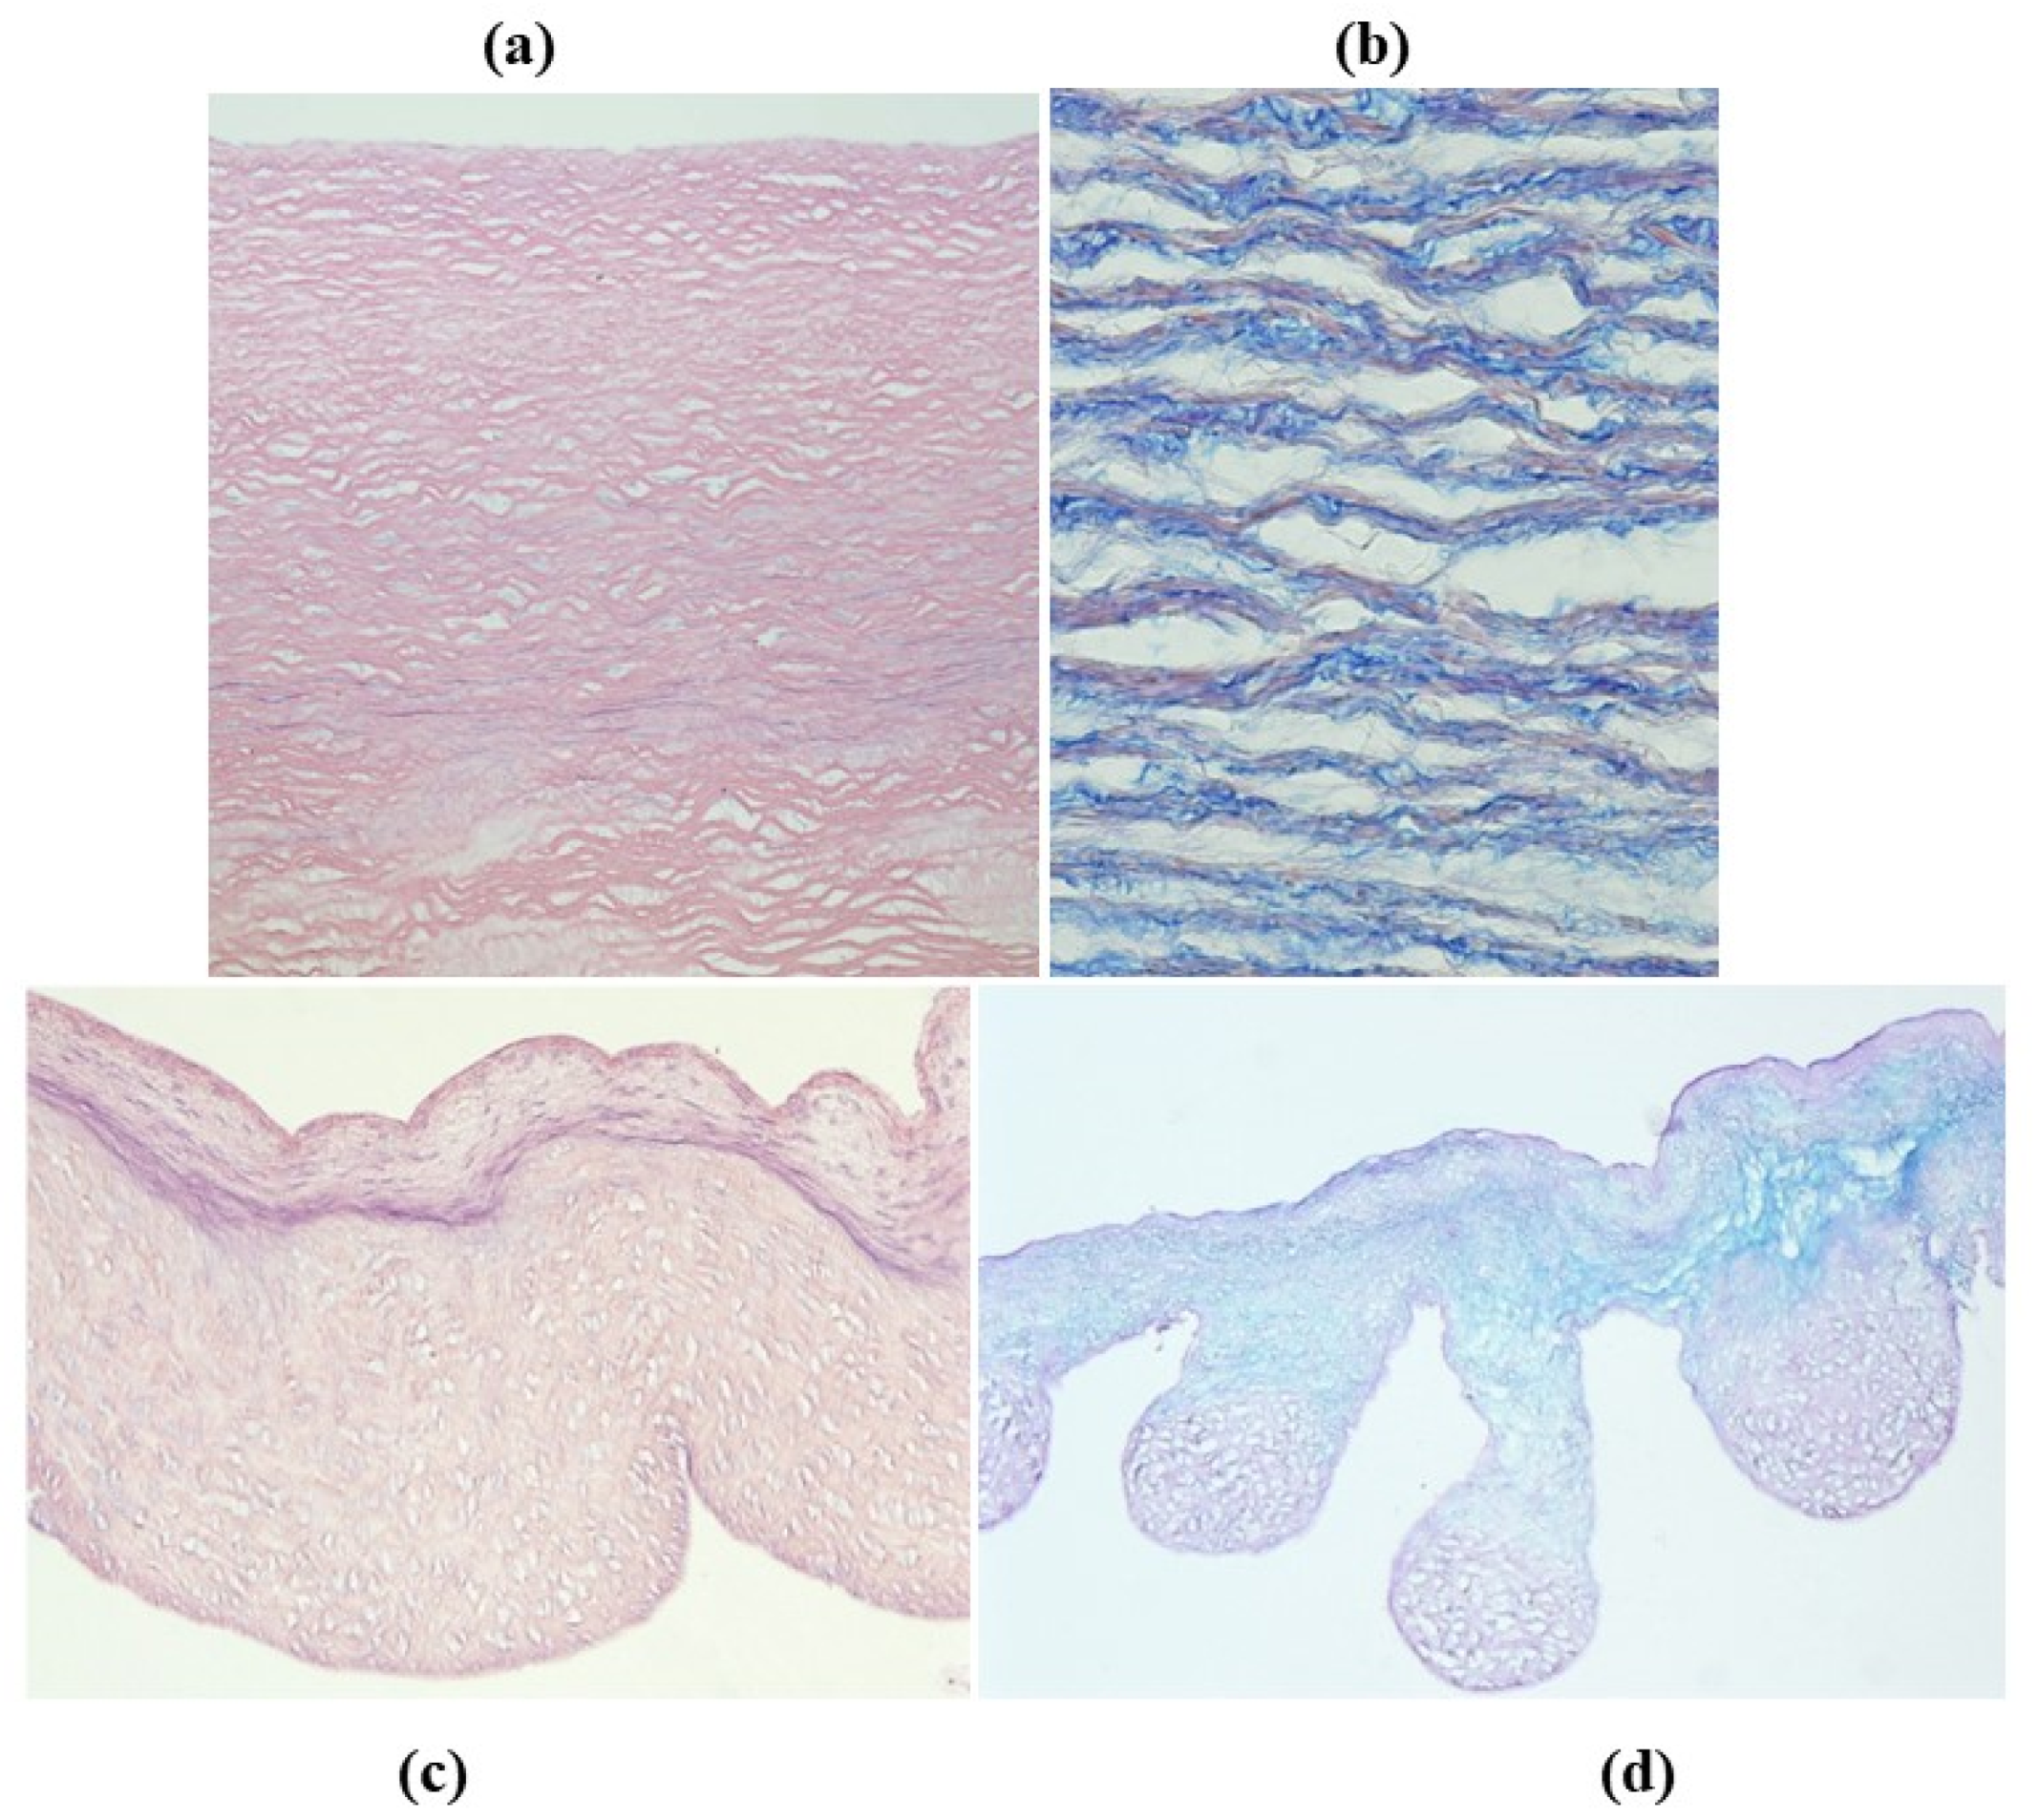

- Decellularization in unimplanted allografts appeared complete, both in the lamellar units of the tunica media and valvular interstitium with disappearance of endothelial lining (Figure 31);

- Cellular repopulation was observed in the outer part of implanted homograft wall by novel smooth muscle cells in the lamellar units (Figure 32a,b) and in the intima with a novel myointimal layer; this layer was noticed also in small animals such as rodents [68]. Novel endothelial cells appeared to line both the aortic wall intima and inflow/outflow at the cusp surface, as well as vasa vasorum, and valve spongiosa appeared repopulated by interstitial cells (Figure 32c,d);